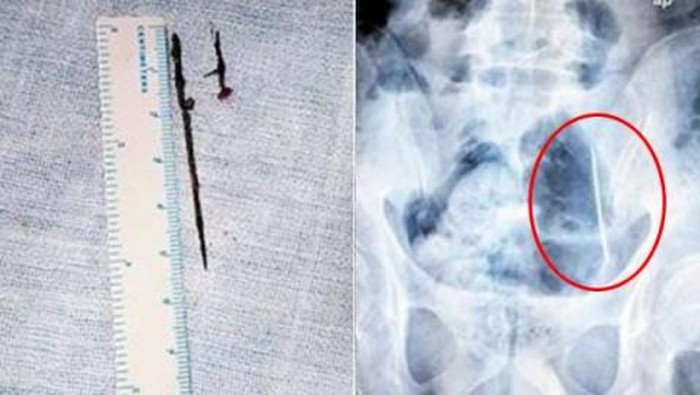

Akan tetapi setelah beberapa kali dilakukan scanning, posisi kedua jarum itu berubah. Padahal bila jarum-jarum itu dapat bergerak kesana-kemari, ada kemungkinan organ dalam pasien terancam bahaya karena dapat menusuk sewaktu-waktu.

Media setempat, People.cn., bahkan melaporkan jarum-jarum itu juga telah berkarat sehingga bisa memunculkan risiko infeksi. Oleh karena itu, tim dokter merasa harus bergerak cepat dengan melakukan operasi pengangkatan kedua logam tersebut.

Operasi pun berhasil dilakukan. Jarum sepanjang 2 cm diambil ketika posisinya berada di dekat rongga perut, sedangkan jarum satunya ditemukan di dalam rongga perut.

Setelah berhasil mengeluarkan keduanya, tim dokter lalu mengamati jarum-jarum itu. Mereka kemudian sampai pada kesimpulan bahwa logam ini diperkirakan sudah 'tinggal' di dalam perut Wu selama dua tahun.